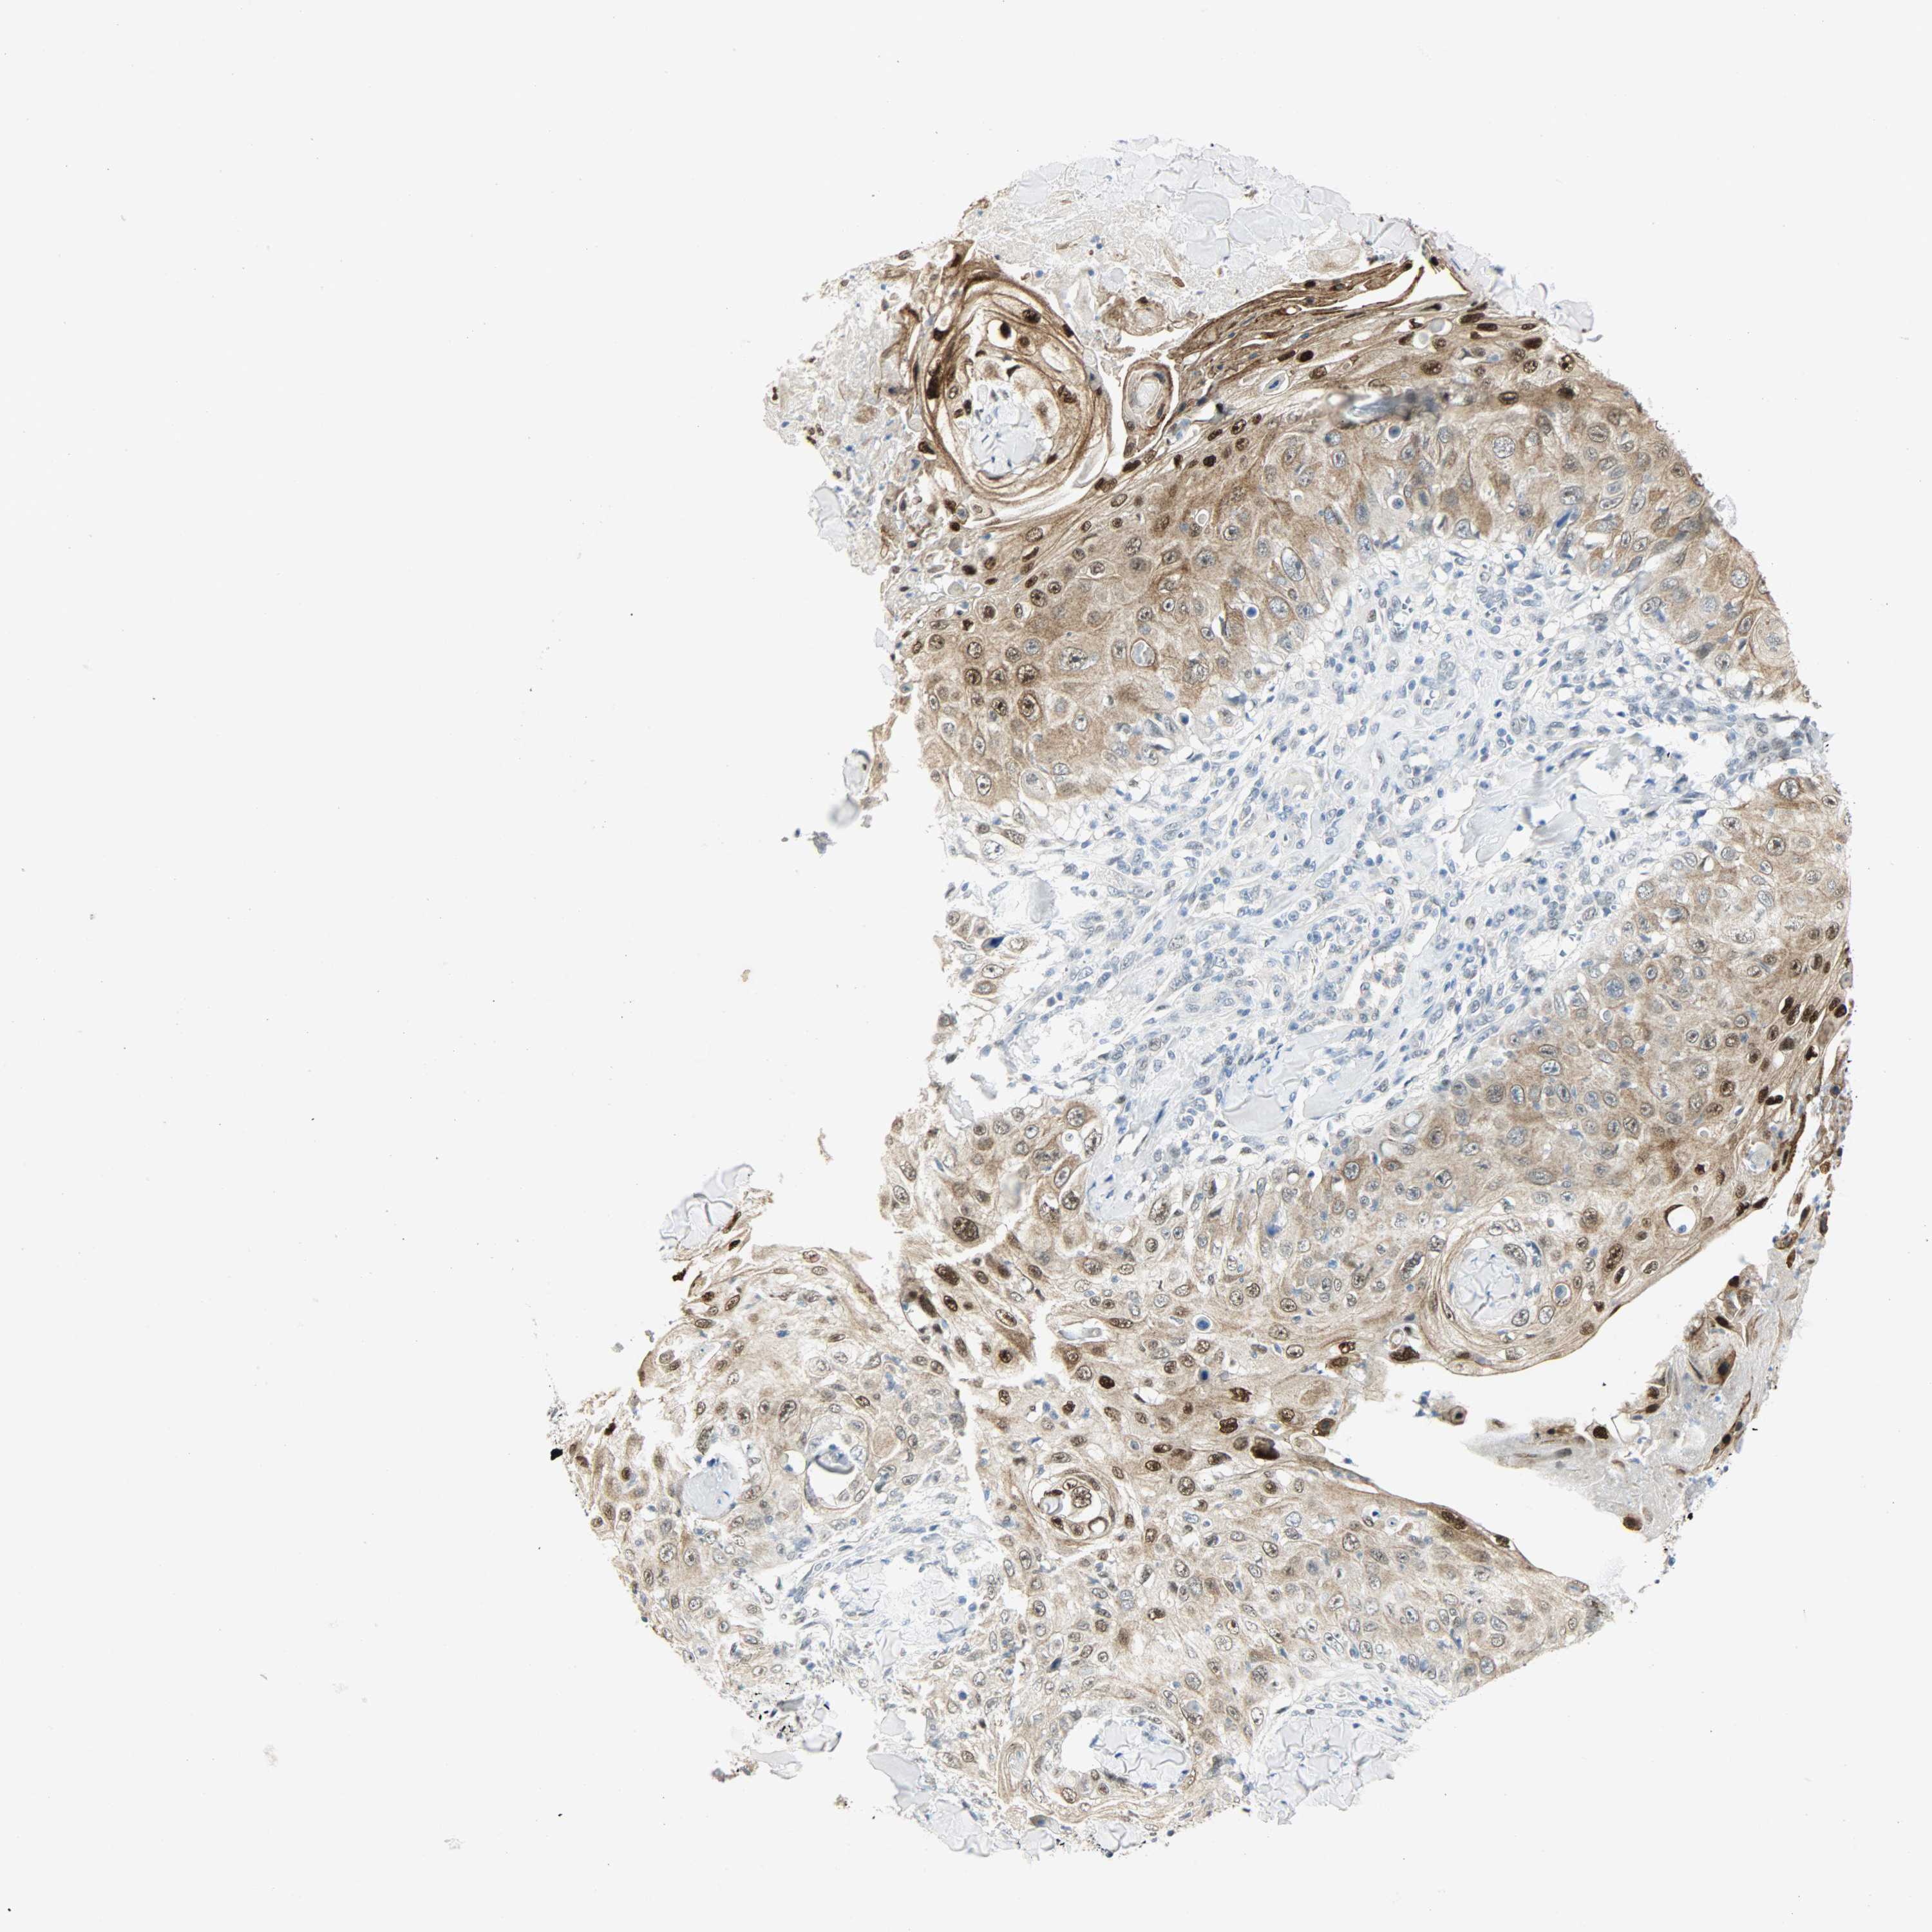

SKIN CANCER - Protein expressioni

A mouse-over function shows sample information and annotation data. Click on an image to view it in a full screen mode. Samples can be filtered based on level of antibody staining by selecting one or several of the following categories: high, medium, low and not detected. The assay and annotation is described here.

Antibody stainingi

Antibody staining in the annotated cell types in the current human tissue is reported as not detected, low, medium, or high, based on conventional immunohistochemistry profiling in selected tissues. This score is based on the combination of the staining intensity and fraction of stained cells.

Each image is clickable and will lead to virtual microscopy that enables deeper exploration of all samples and also displays staining intensity scores, fraction scores and subcellular localization as well as patient and tissue information for each sample.

Antibody CAB004282

Staining

High

Intensity

Strong

Moderate

Quantity

>75%

75%-25%

Location

Nuclear

Cytoplasmic/membranous

Cytoplasmic/membranous,nuclear

Squamous cell carcinoma, NOS